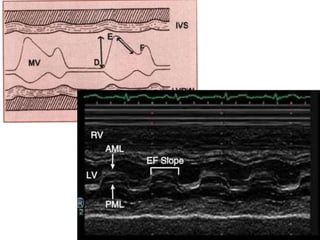

M mode

1. Dense echo on MV

2. Decreased D-E excursion

3. Poor leaflet seperation

4. Anterior motion of posterior leaflet

5. Decreased E-F slope

M mode 1. Denseecho on MV 2. Decreased D-E excursion 3. Poor leaflet seperation 4. Anterior motion of posterior leaflet 5. Decreased E-F slope